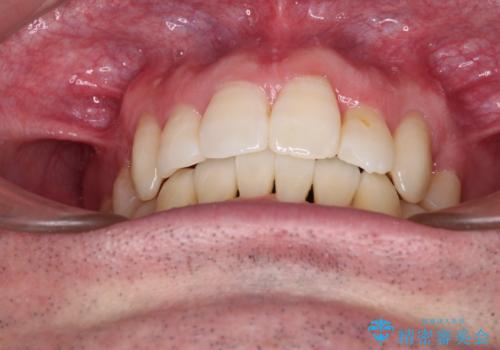

ものが挟まる 著しい叢生を解消 ワイヤー装置による抜歯矯正

- 前歯のデコボコを気にして来院された患者様です。

叢生の解消とともに、前方に張り出した上顎前歯を引っ込めることを目的とし、上下左右の第一小臼歯4歯を抜歯をしてワイヤー矯正により治療することとしました。

治療開始直後は、あっという間に歯列が整い、すぐに終わるのではないかと思われましたが、治療の後半にブラックトライアングル解消のための処置を行ったため、当初予定していた2年半ほどの期間を要することとなりました。